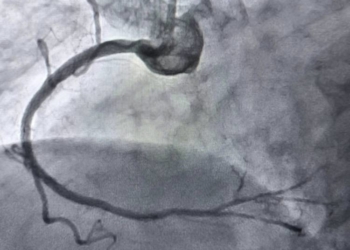

Тернопільські хірурги навчилися чистити артерії за допомогою «космічних» технологій

Медицина в Тернополі зробила ще один впевнений крок у майбутнє. Нещодавно наші хірурги провели операцію, яка ще кілька років тому ...